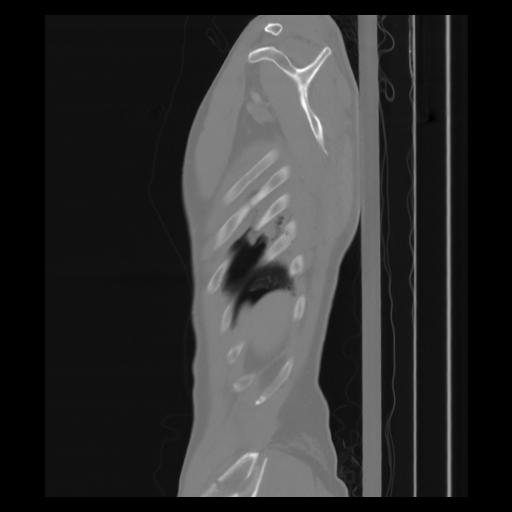

30 CUERPO,CE,Sagittal,3.000,CUERPO,Sagittal,